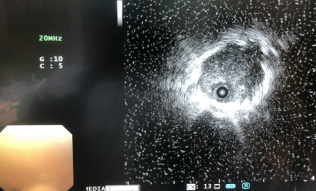

径向超声支气管镜下肺组织者活检术(EBUS-GS-TBLB)